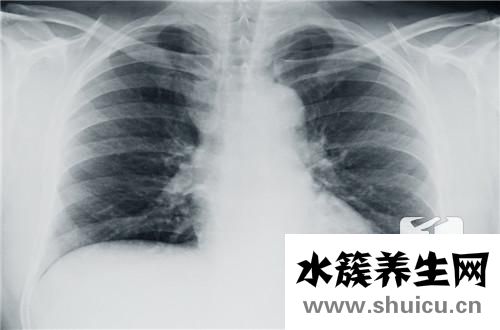

一般檢查有許多項目,包括化學檢查和儀器檢查。我們通常看到的是x光檢查、b超檢查和核磁共振檢查。這三種檢查是不同的,側重點不同,價格也不同。核磁共振檢查費用較高,主要是從橫切面檢查病變核磁共振...